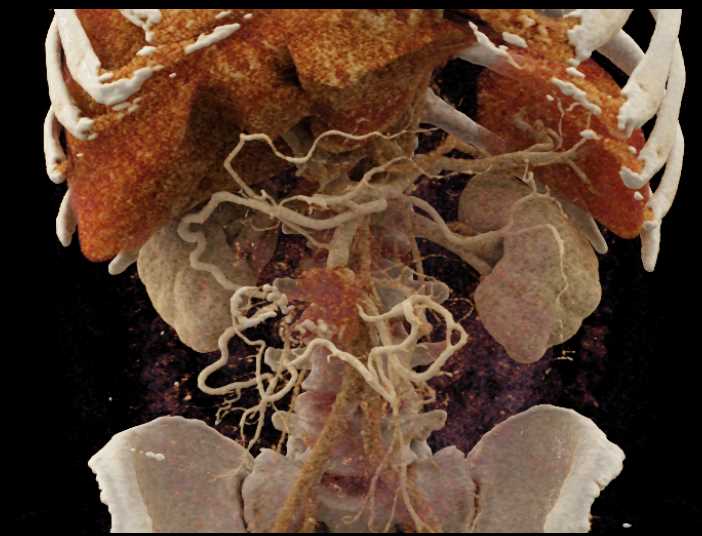

Carcinoid Tumor with Desmoplastic Reaction